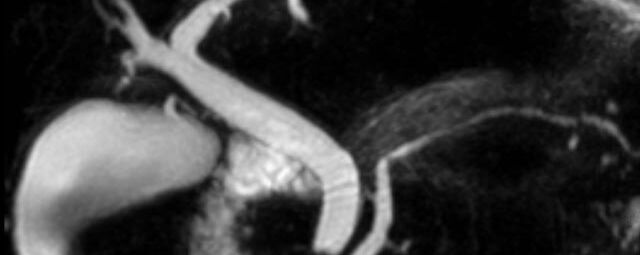

Herz/Thorax

Herz

Durchführung am Standort im Diakonissenkrankenhaus.

• kardiale Ischämiediagnostik mit medikamentöser Stress-MRT (Adenosin)

• Infarktnarbendarstellung/Vitalität

• Kardiomyopathien (z.B. Myokarditis, DCM, HCM/HOCM, Amyloidose, Sarkoidose)

• Klappenbeurteilung mit Phasenkontrastangiographie

• Tumoren Herz und Mediastinum

• Fehlbildungen

• MR-Angiographie zur Erfassung und Verlaufskontrolle von Aneurysmen der Aorta thorakalis und ihrer Gefäßabgänge